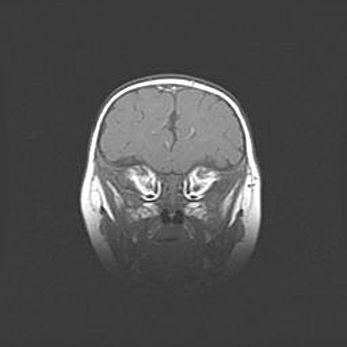

Открытая гидроцефалия.

Возраст: 9 месяцев 12 дней

Вес: 6800 г

Пол: мужской

Окружность головы: 41,5 см

Срок гестации: 28 недель

Гидроцефалия головного мозга у новорожденных имеет характерный признак: опережающий рост окружности головы приводит к визуально хорошо определяемой гидроцефальной форме сильно увеличенного в объёме черепа. Детские неврологи определяют следующие симптомы гидроцефалии у грудничков: выбухающий напряжённый родничок, частое запрокидывание головы, смещение глазных яблок к низу.